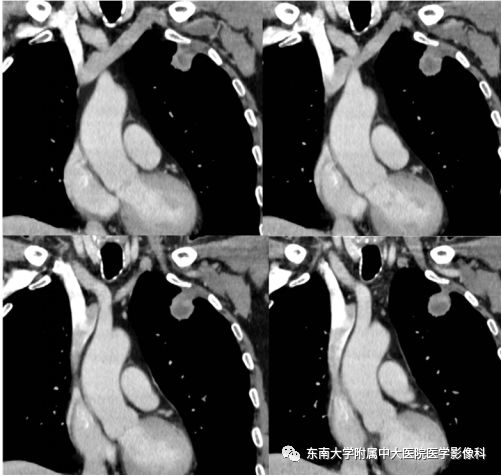

男,70岁,因“腹痛2月余,发现胃窦病变9天”入院

病例结果:病例1:机化性肺炎;病例2:肺腺癌